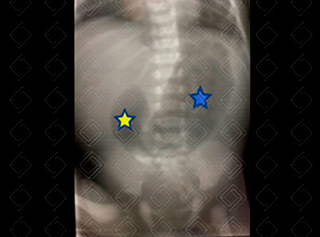

Texto alternativo para a imagem Créditos: Dra. Elazir Mota - Rio de Janeiro/RJ

Descrição da lesão: Radiografia de abdome. O asterisco azul evidencia estômago distendido e o asterisco amarelo evidencia duodeno proximal, também distendido por gás.

Sinal da dupla bolha ( double-bubble sign ): Caracteriza-se pela presença de bolha, proximal, à esquerda, que representa o estômago repleto de gás, e outra bolha, distal, à direita, que representa distensão do duodeno proximal.